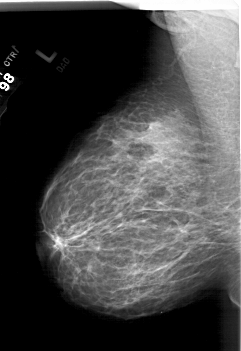

A_1779_1.LEFT_MLO

LEFT_MLO LINES 6316 PIXELS_PER_LINE 4336 BITS_PER_PIXEL 12 RESOLUTION 43.5 NON_OVERLAY